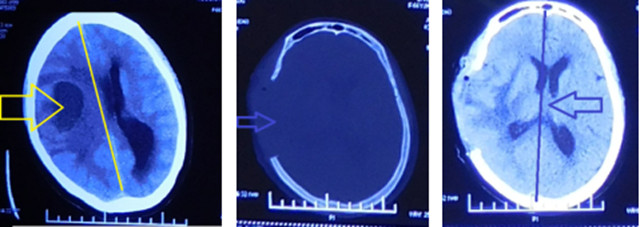

患者回家10天后突发昏迷,随拨打县一院急诊电话,通过急诊绿色通道,进行头颅CT(黄色箭头示肿瘤组织,有液化坏死及线移位 ),患者右侧瞳孔散大,已形成脑疝,呼吸困难,立即进行气管插管,神经外科医疗团队随即精心设计治疗方案,通过与患者家属充分沟通,在急诊全麻下迅速进行了“去骨瓣减压+肿瘤切除术”,手术顺利。术后复查头颅CT示:(蓝色箭头)骨瓣去除及中线复位。